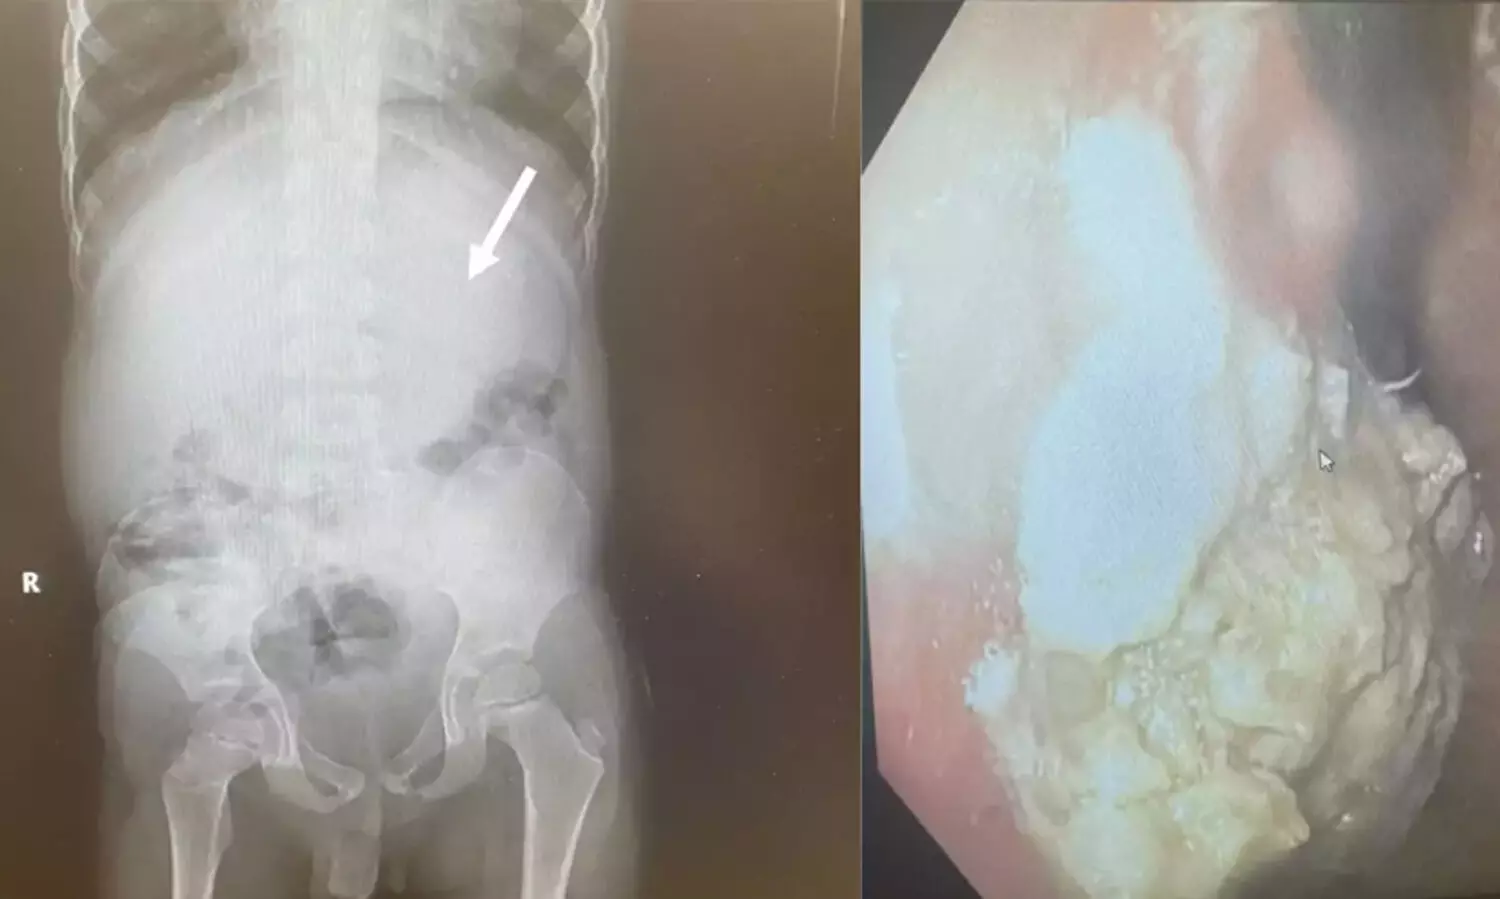

വിഴുങ്ങിയത് 40 ച്യൂയിംഗ് ഗം; അഞ്ചു വയസുകാരന് അടിയന്തര ശസ്ത്രക്രിയ